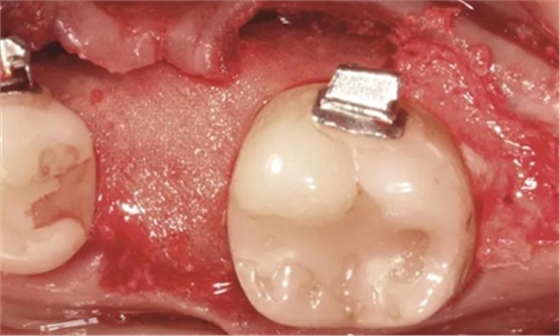

手術(shù)切口位于牙槽嵴頂舌側(cè),溝內(nèi)切口向下頜升支的遠(yuǎn)中和頰側(cè)延伸,接著翻全厚粘骨膜瓣。牙槽嵴去皮質(zhì)術(shù)在下頜第一磨牙受區(qū)和第二磨牙牙根遠(yuǎn)中進(jìn)行,用一個(gè)高速的碳化鎢鋼球鉆和超聲骨刀進(jìn)行(Piezosurgery, Mectron)(圖2b)。

翻起頰側(cè)瓣后,放置同種異體凍干骨(freeze-dried bone allograft,F(xiàn)DBA),并覆蓋可吸收膠原膜(Osseoguard, Biomet 3i)(圖2c)。第二磨牙遠(yuǎn)中去皮質(zhì)區(qū)上放置硫酸鈣(CaSO4, ACESurgical)。瓣主要采用5-0聚四氟乙烯縫線(xiàn)進(jìn)行水平褥式和牙間間斷縫合,以及連續(xù)縫合(GORE-TEX, W.L.Gore & Associates)。

圖2b.增量時(shí),在受區(qū)和右下第二磨牙遠(yuǎn)中進(jìn)行牙槽嵴去皮質(zhì)術(shù)

圖2c. 移植處用膠原膜保護(hù),磨牙后區(qū)用硫酸鈣覆蓋

圖5c. 翻全厚瓣后,看到嚴(yán)重的牙槽嵴吸收

圖5d. 在骨移植受植處、第二磨牙和第三磨牙牙根之間以及第三磨牙遠(yuǎn)中進(jìn)行去皮質(zhì)術(shù)

圖5e. 去皮質(zhì)后,同種異體凍干骨顆粒放置于受植區(qū)

圖5f. 膠原膜覆蓋并適應(yīng)于受植區(qū)